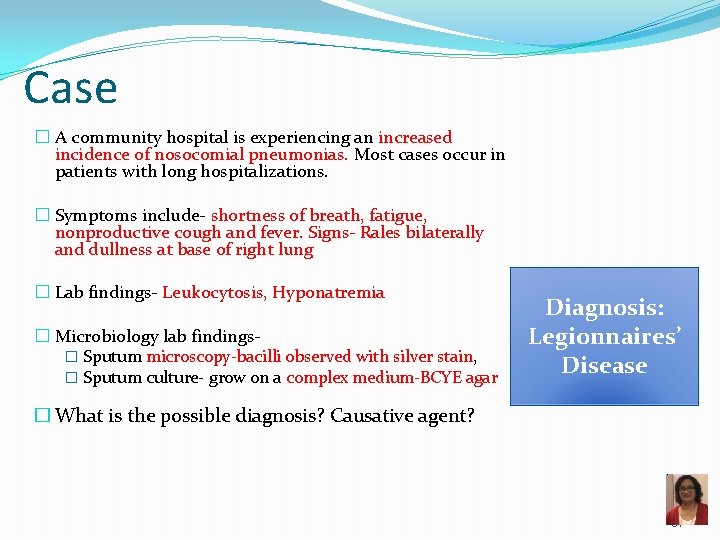

Case � A community hospital is experiencing an increased incidence of nosocomial pneumonias. Most cases occur in patients with long hospitalizations. � Symptoms include- shortness of breath, fatigue, nonproductive cough and fever. Signs- Rales bilaterally and dullness at base of right lung � Lab findings- Leukocytosis, Hyponatremia � Microbiology lab findings� Sputum microscopy-bacilli observed with silver stain, � Sputum culture- grow on a complex medium-BCYE agar Diagnosis: Legionnaires’ Disease � What is the possible diagnosis? Causative agent? 91